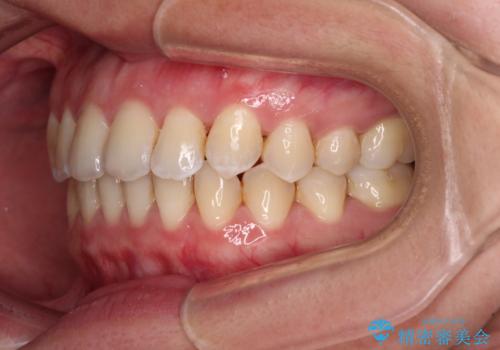

前歯の反対咬合 急速拡大装置とワイヤー装置であっという間の矯正治療

- 全顎的なクロスバイトと反対咬合を気にして来院された患者様です。

骨格的に下顎が前方位にありましたが、歯並びにより下顎が本来の位置よりも前方位に誘導される咬み合わせとなっていました。

上顎歯列および上顎骨が下顎に対して狭小であることが原因であるため、上顎の急速拡大装置を使用して上顎骨を側方に拡大することで反対咬合を改善し、ワイヤー装置で歯列を整えることとしました。

上顎の拡大に伴い反対咬合があっという間に改善されました。

元々の歯列不整は軽微であったため、僅か1年の期間で治療を終えることができました。